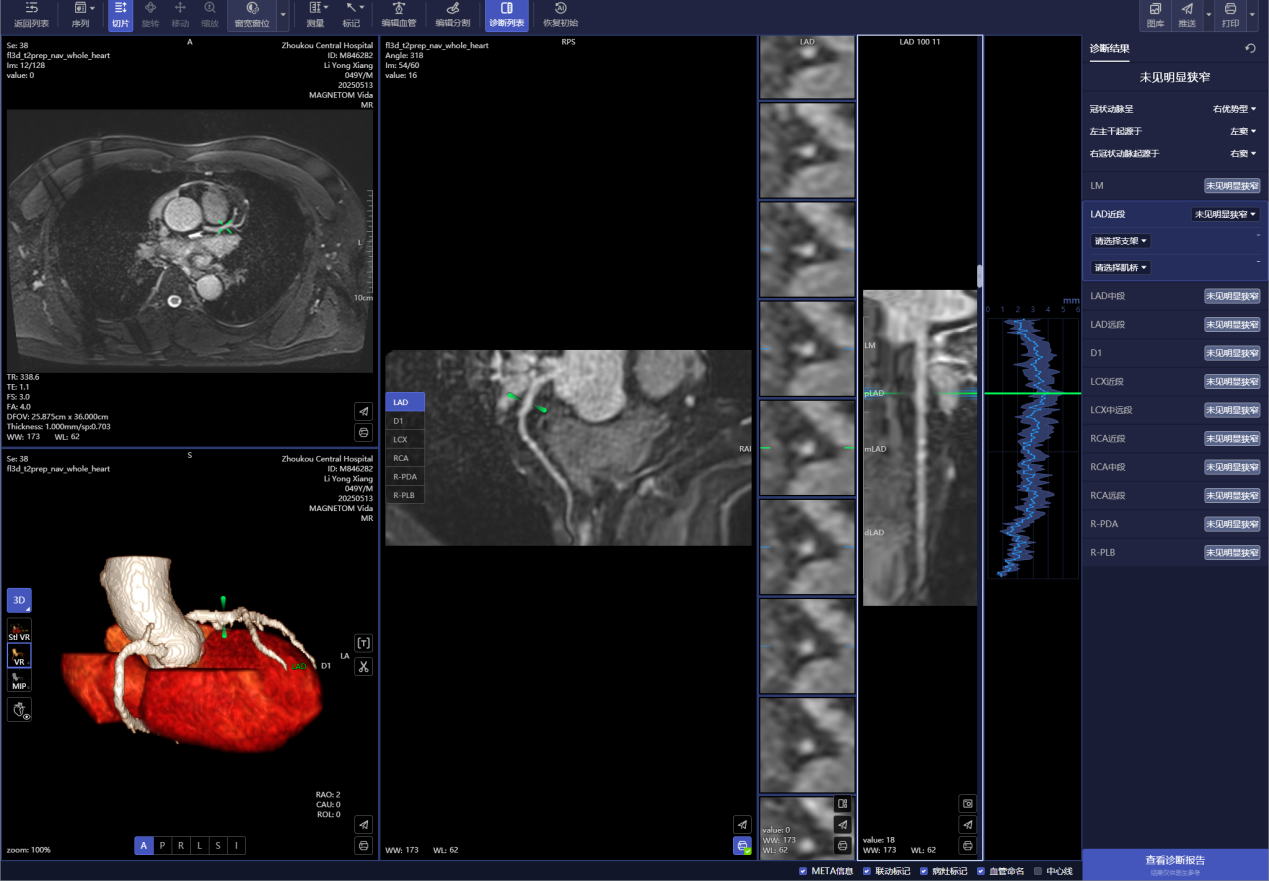

人工智能:强大的人工智能软件可以精确的判断血管的狭窄程度及位置,甚至可以为介入手术提供手术方案

三、检查能发现什么危险信号

1. 血管堵没堵:

- 就像检查水管有没有锈迹,能看清血管狭窄程度

- 提前发现血管里的“垃圾”(斑块),特别是那些容易破裂的危险斑块

2. 心肌伤没伤:

- 曾经发生过小范围心梗留下的疤痕

- 评估心肌缺血的区域,帮助判断是否需要放支架

3. 心脏功能:

- 精确计算心脏每次跳动泵出多少血液

- 发现心肌变厚(肥厚型心肌病)或扩大(扩张型心肌病)